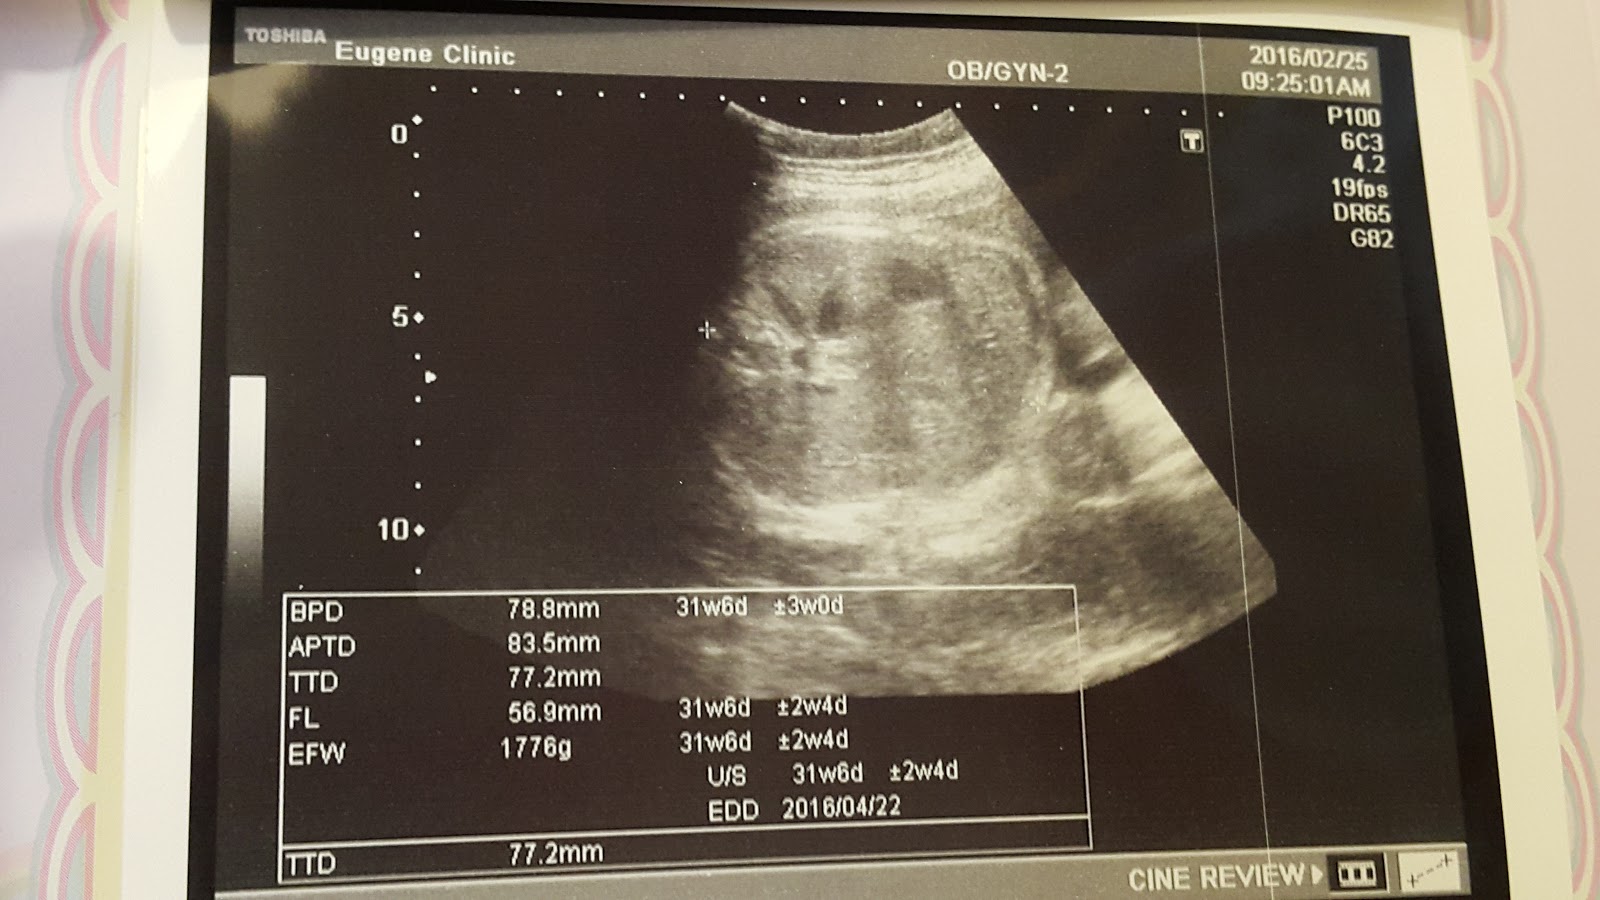

Haru長的頭好壯壯,目前1700多克,是正常體重

電腦的預產期跟醫生評估的差不多

一切指數都有按標準來成長